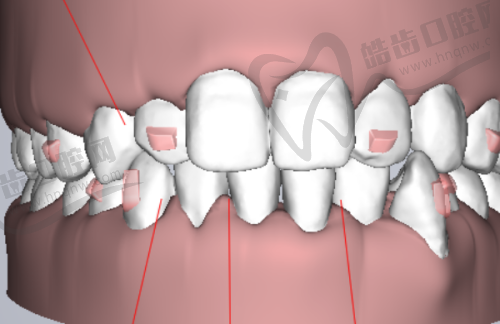

牙齿贴面树脂牙能挺多久是特别多想要做牙齿贴面的人关心的问题。一位有5年树脂牙贴面使用经验的过来人告诉你,树脂牙贴面一般使用年限在3 - 5年左右。不过这个时间并非固定不变,它受到多种因素的影响,像个人口腔卫生习惯、饮食习惯、牙贴面的材料质量以及医生的修复技术水平等。下面我们就来详细了解一下树脂牙贴面使用年限的相关情况。

树脂牙贴面是一种用于美容修复牙齿的材料,能改善牙齿的色泽、形状和大小等问题,比如做牙体缺损修复、补牙缝等。一般来说,树脂牙贴面的使用年限为5年左右,但也有资料显示其寿命在3 - 5年。

不同质量的树脂牙贴面材料,其使用年限会有明显差异。质量好的树脂牙贴面,其稳定性和耐磨性相对较好,能够承受日常的咀嚼压力和摩擦,不容易出现磨损、崩边等情况。

比如一些进口的优质树脂牙贴面材料,它们在制作工艺和成分上更加精细和科学,能够更好地抵抗口腔内的酸碱环境和细菌侵蚀,从而延长使用年限。